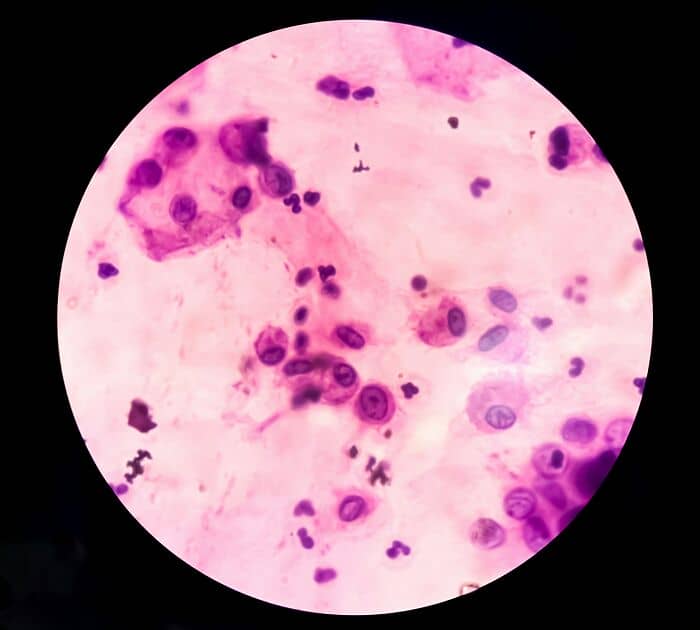

Well, there’s the whole thing about prions and their effect upon the brain. That’s spooky.

throwaway_78325:

As someone in healthcare, prion diseases. The more I learn about them the more I spiral. The random/genetic variants are the scariest but I live in an area where the majority of my friends husbands/boyfriends are hunters and bring home game meat and absolutely not, I politely decline any sort of meat they’re serving at their house. Keep that away from me.

noctenaut:

Prions.

Tiny little proteins inside your brain, they replicate themselves by folding and then forming out another prion.

Sometimes, they fold incorrectly, and then cause other prions to do the same – eventually, widespread misfolded proteins cause damage to the brain, and introduce prion diseases such as ‘Mad Cow Disease’ or ‘Fatal Insomnia’.

Prion diseases are unique, most pathogenic illnesses are caused by foreign bacteria, viruses, parasites and other tiny organisms – but prion diseases are caused by agents of your own body, not foreign.

As such, where antibiotics, antivirals and other means of therapy against a pathogen are largely effective – no such therapy exists against prion diseases. Cases are always fatal. A good example is fatal insomnia – as the prions damage the brain further and further, the ability to sleep becomes impossible and the victim must wait for the body to give up. Hell on earth.

Prions are also incredibly hard to destroy, being resistant to alcohol, radiation, boiling, freezing and other conventional sterilisation methods – sometimes slipping into the food chain via farm animals such as cows, (hence ‘Mad Cow Disease’).

The also differ from other pathogens in that a misfolded prion overrides other proteins’ normal behaviour and thus causes them to misfold too. No other pathogen has the same ability – weaponising your own tissue against you.

As such, the central nervous system and eye tissue of somebody with a prion diseases is extremely contagious and require specialist destruction.

#31

Fatal familial insomnia. Its a prion disease where your brain slowly loses the ability to sleep. Not like regular insomnia where you’re tired but eventually crash – your brain literally forgets how to fall asleep. Average survival after symptoms start is like 12-18 months, and the whole time youre completely aware of what’s happening to you. No cure, no treatment, nothing. Your brain just deteriorates while you’re awake watching it happen.